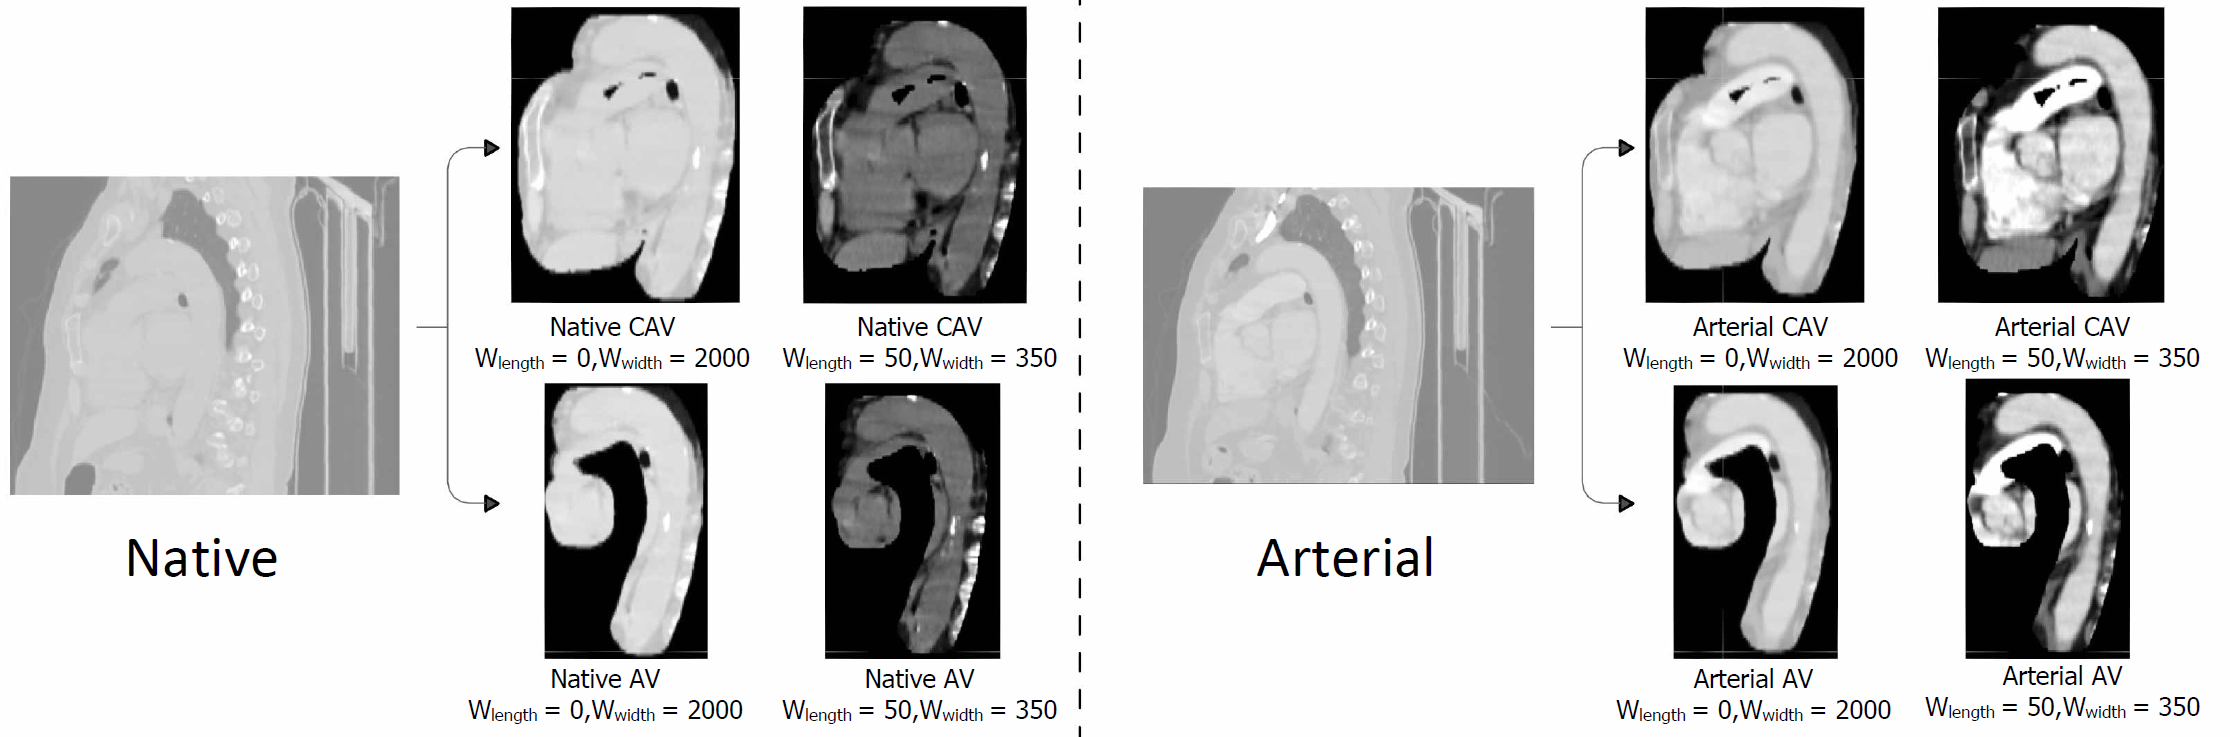

In this work, we use the SyN (Symmetric Normalization) registration method [1] to align the non-contrast and contrast-enhanced images. Before registration, we removed structures unrelated to the aorta and its immediate cardiac context such as the spine and abdominal organs using segmentation-based cropping. This step ensured that registration focused on the thoracic vascular region and reduced interference from irrelevant anatomy. After registration, to provide the model with contextual information about tissue characteristics, we retained controlled surrounding regions by applying mask dilation rather than restricting the input to the aorta alone. Figure 2 presents the sagittal view of the middle slice of one sample along with the pre-processed results. The original input scans are processed into two datasets, Cardiac-Aortic Volume (CAV) and Aortic Volume (AV), using segmentation masks to simulate different level of background tissue around the aorta. The AV dataset includes only the aorta and its surrounding region, defined by a 10 voxel dilation of the aorta segmentation mask obtained via the TotalSegmentator tool [9]. The CAV dataset extends this region to include the myocardium, left and right atria, and left and right ventricles, with a 20 voxel distance dilation. For both native and arterial images, we apply the union of all arterial and native segmentation masks to ensure consistency across datasets.

Refer to caption

Figure 2: Pre-processing for native and arterial CT images. The original inputs are processed into two datasets: CAV and AV, where cropping is performed using dilated segmentation masks. The sample is also visualized under two windowing settings: Full HU range and Soft Tissue Window, highlighting different tissue structures.